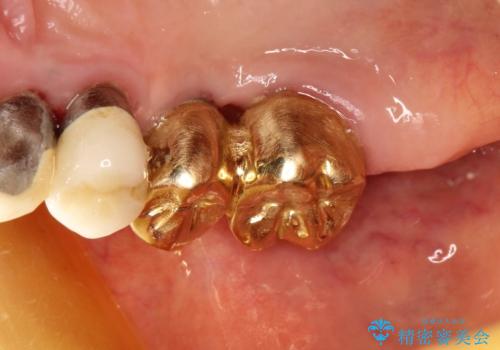

- 破折により保存不可能となった歯を抜歯後、待時してインプラントを計画した。

骨が薄く、インプラントの径に耐え得ないと判断したためスプリットクレストにより骨幅を拡大しインプラントを埋入した。

スプリットクレストやリッジエキスパンジョンといった方法は、骨が薄く、細い場合に、割線を設定し、狭い骨幅を拡大すると同時にインプラントを埋入することができます。